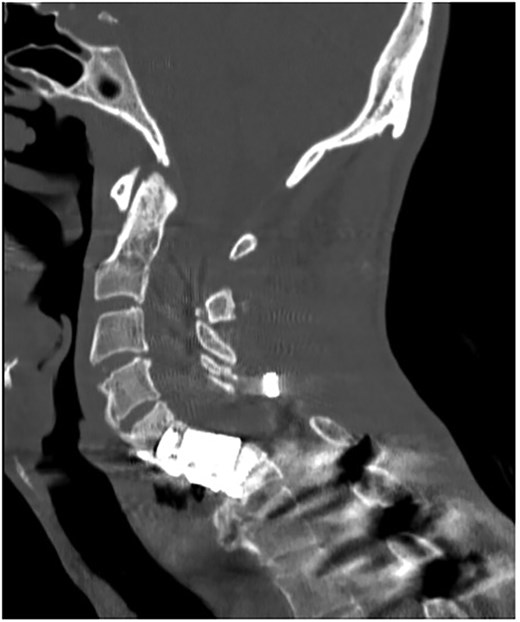

A 35-year-old male presented with a month-long history of dysphagia, severe headache, and posterior neck pain that radiated to the occiput. His medical history was significant for cervical surgeries, including an anterior cervical discectomy and fusion (ACDF) at C5/C6 one year and two months ago (Fig. 1). Shortly thereafter, the patient underwent revision surgery along with posterior plating from C5 to T1 due to osteomyelitis, worsening cervical deformity, and retropharyngeal abscess (Fig. 2). Initial workup included a noncontract computed tomography (CT), demonstrating increased gas density at C6 corpectomy site and post cricoid region (Fig. 3). A swallow study was obtained based on suspicion of a perforation and demonstrated extraluminal leakage of contrast posteriorly at the C6 level, consistent with initial CT (Fig. 4). Surgery included removal of the anterior and posterior hardware and esophageal repair. Although initially the esophageal injury was suspected to be related to the hardware, intraoperatively, it was found the instrumentation was not in communication with the esophagus. This confirmed the perforation was unrelated to direct injury from the cervical hardware construct, which was intact. The esophagus was repaired with a pectoralis flap. The postoperative course was uneventful, and the patient was discharged home after one week. The patient later died due to severe complications of substance abuse unrelated to the operation.

Swallow study demonstrating extraluminal leakage of contrast posteriorly at the C6 level consistent with CT findings.